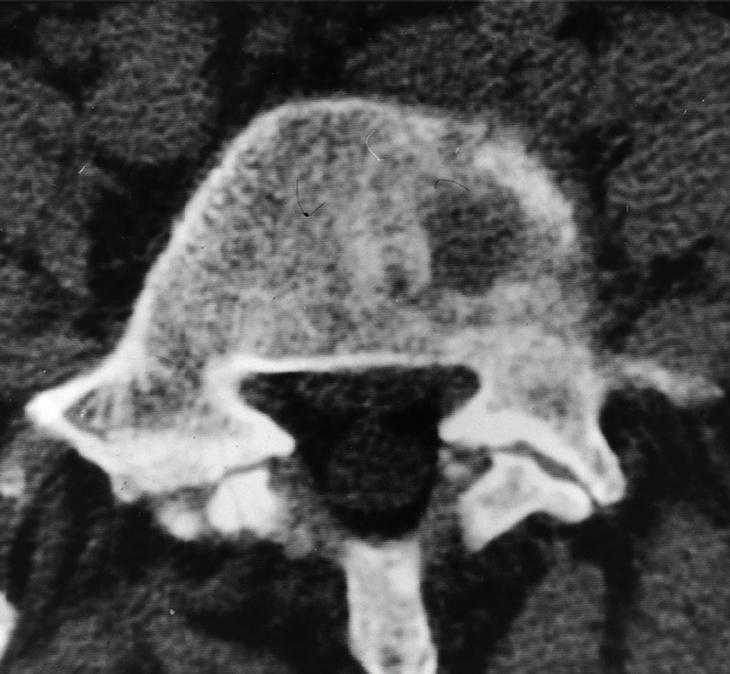

Los controles radiológicos de la vertebroplastia se realizan con radiología simple (fig. 1) y con TC (figs. 2A y 2B).

En la radiografía el hemangioma presenta características estriaciones óseas groseras y verticales en el cuerpo vertebral separadas por zonas radiolúcidas. En TC las estriaciones groseras se presentan en forma de imágenes puntiformes hiperdensas dentro de un área de rarefacción ósea. En RM el hemangioma se presenta como una lesión hiperintensa en las secuencias potenciadas en T1 y T2. El aumento de señal en T1 es debido al componente graso de la lesión, mientras que la hiperintensidad en T2 es debida al componente vascular.

En una lesión vertebral, la TC revela una lesión hipodensa, osteolítica que afecta fundamentalmente al cuerpo vertebral respetando los pedículos. En muchas ocasiones se puede observar gran extensión hacia el espacio paravertebral y epidural. La TC descarta la existencia de calcificaciones intratumorales.